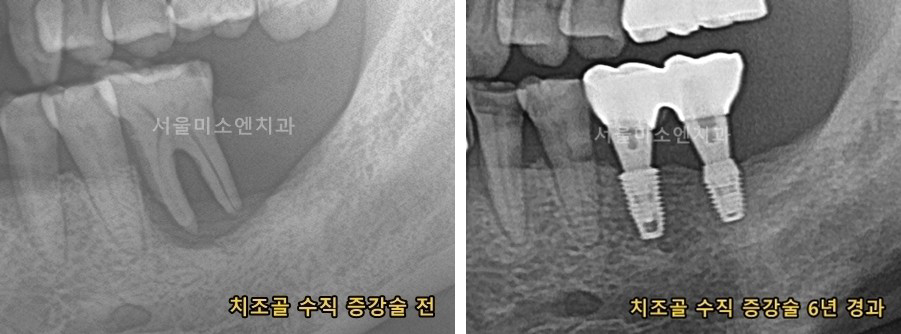

하지만 치조골 이식 수술이 한번에 완료되지 않습니다. 벌써 이식만 3번째입니다. 1번째, 2번째는 임플란트 비용 제외하고 30만 원을 추가로 지불했었습니다.

이번 3번째는 임플란트 130만원에 치조골 수술비용 35만 원으로 총 165만 원이 들었습니다. 여기서 재료 비용을 절약하는 방법은 발치된 자신의 치아를 활용할 수 있습니다. 이 부분은 치과에 문의하시기 바랍니다.